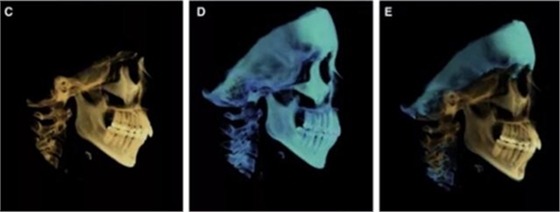

頭側(cè)分析提示為骨性安氏II類(ANB,8.4°;Wits,3.6mm),高角(SN-MP,44.9°),上頜切牙略舌傾(U1-SN,96.2°),下頜切牙略舌傾(IMPA,88。3°)(圖2;表)